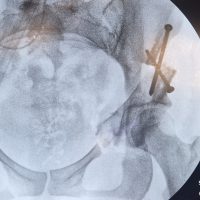

Information complète à destination des patients Cette page d’information médicale a pour objectif de vous expliquer de façon claire, détaillée et accessible ce qu’est l’ostéotomie périacétabulaire (OPA). Vous y trouverez des explications sur l’anatomie de la hanche, la dysplasie, les raisons pour lesquelles une ostéotomie peut être proposée, la préparation à l’intervention, le déroulement précis de l’opération, les suites post-opératoires,...